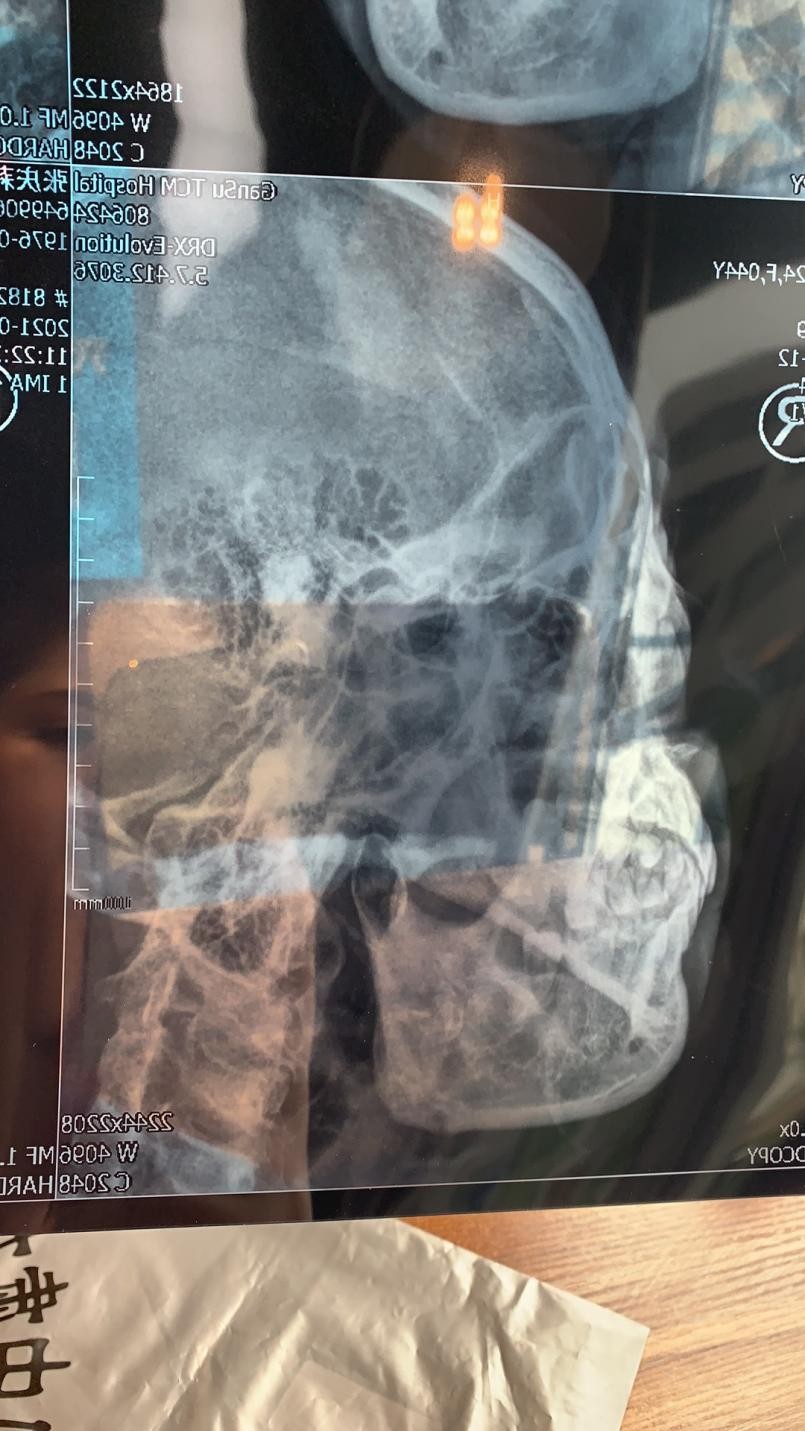

走出美容院后x女士实在忍受不了肋骨的剧痛便赶往了附近的甘肃中医院拍片 , 而后又将此片发给了珊珊店长 , 对此焕颜美容院的回应是可能是皮下的筋网被拉断了 , 让x女士热敷 。

(此为x女士肋骨拍片及珊珊店长的回复)